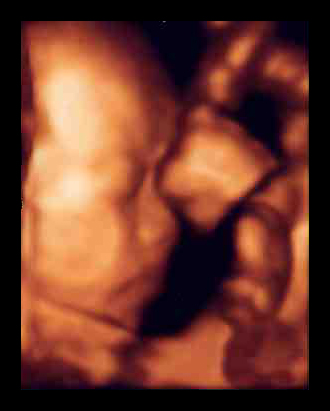

先生の説明だと、モノが立体に見える「3D画像」を時間を追ってみられるから「4D」と呼ぶんだそうです。1秒間に6回画像が更新されて、映像を見ているみたいにリアルなんだって。手で顔をこすったり、あくびをしたり、足を握ったリ、キックしたり。しかめ面や微笑む顔まで、よーくわかるらしいの。ママの臍帯を握って安心している様子も見られちゃう(下写真)。ママは「ああ、お腹の中で生きてるんだなあ」って実感がわいて、とても感動するみたい。